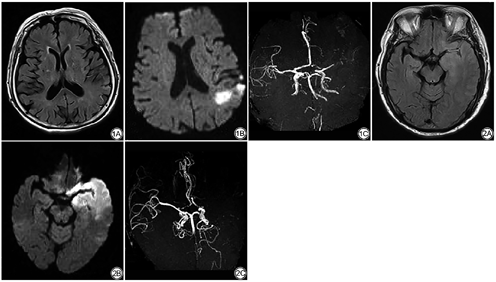

A组患者的脑侧支循环代偿分级、DWI-ASPECTS评分均小于B组,脑梗死体积大于B组,差异比较有统计学意义(P<0.05;表2)。典型病例见图1、2。